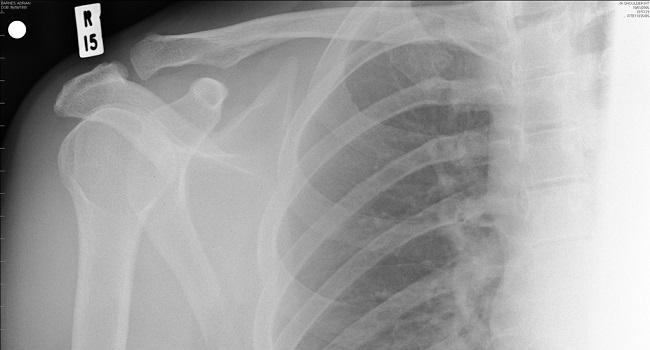

#4 X-RAY IMAGING

Since then, X-rays have had many important uses in medicine: doctors use X-rays to study our bones while dentists use X-rays to detect diseases of the teeth. X-rays are also used in radiotherapy to stop cancer cells from growing and multiplying.